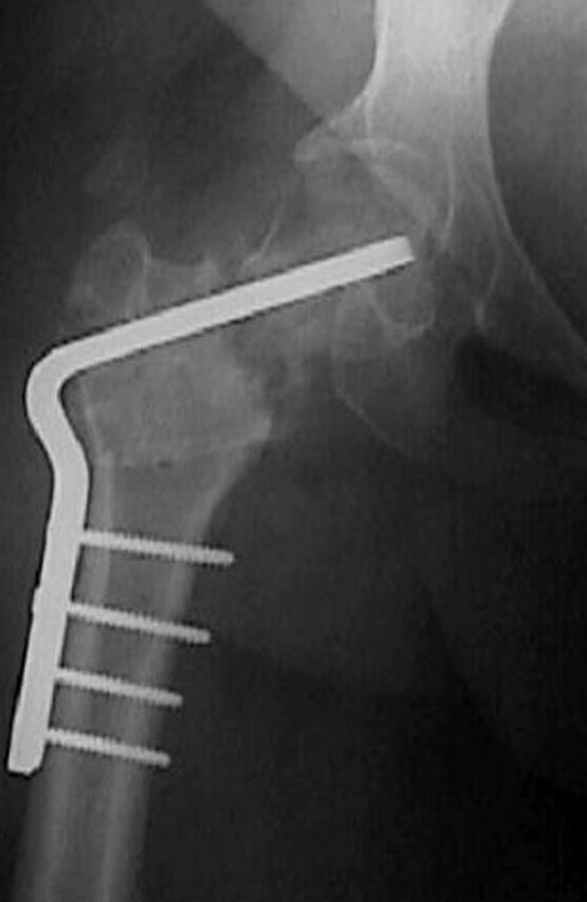

Отправитель: Alexander Chelnokov 23 Ноябрь 2004, 02:31

Если, например, доводится лечить больных с псевдартрозами шейки бедра, то надобность есть, и приходится. См. приложение.

Несколько снимков из моей коллекции, чтобы разьяснить, почему мы до сих пор делаем различные варианты остеотомии.

На рисунке N1 предоперационный план лечения ложного сустава шейки бедра- линия ложного сустава, угол и направление введения импланта, клиновидная остеотомия в градусах и миллиметрах, второй снимок после коррекции, расчет, на сколько удлиняется конечность и размеры импланта;

N3 рисунок окончательный снимок, после операции моя рентгенограмма должен выглядеть примерно как эта картина. На N4 снимке клин перед удалением; N5 послеоперации 3 нед.; N6 окончательная рентгенограмма.

варус при проксимальном отделе 95 градусной пластиной.